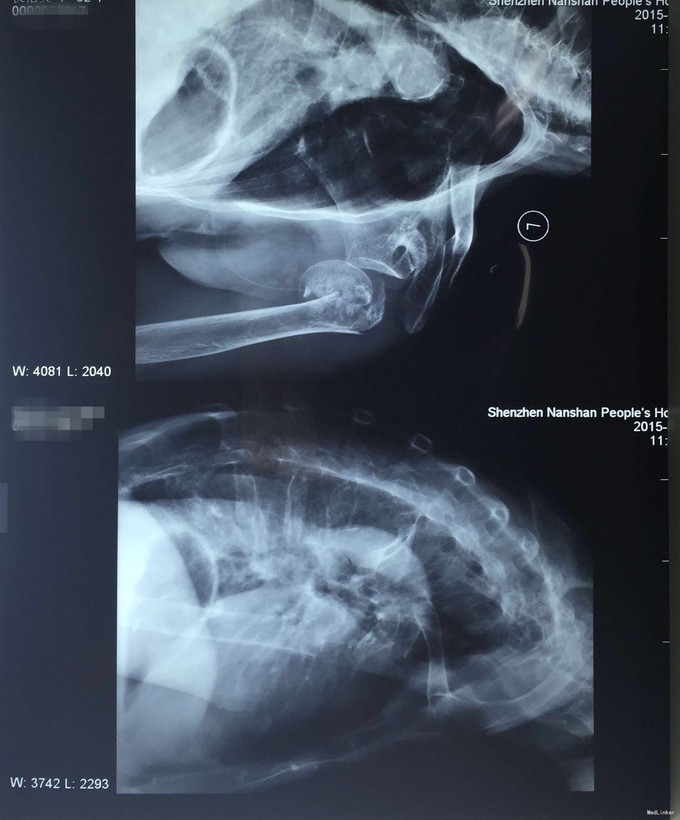

患者,女性,95岁,因“摔伤致左肩部疼痛、肿胀、活动困难4小时”入院。 患者缘于入院前4小时前因不慎摔伤致左肩部受伤,即觉左肩部疼痛、活动困难、肿胀,由家属送往我院就诊,经行X射线提示“左肱骨近端粉碎性骨折”,急诊科未予特殊处理,为做进一步诊治而收入院。患者受伤以来,精神好,无呼吸困难,无恶心、呕吐,无头晕,无大小便失禁史。

体温36.5℃ 脉搏:90次/分 R:20次/分 神清合作,应答切题、全身皮肤黏膜无黄染、浅表淋巴结无肿大,头颅五官无畸形,巩膜无黄染,双侧瞳孔等大等圆,直径3mm,对光反射灵敏。颈软,无抵抗,气管居中,甲状腺无肿大,胸廓无畸形,胸廓挤压痛(-),心前区无隆起,双肺叩诊清音,呼吸清音,无干湿性罗音,心率90次/分,律齐有力,各瓣膜区无病理性杂音。腹平,腹肌软,全腹压痛、无反跳痛,肝脾肋下未及,双肾区无叩痛,无移动性浊音,肠鸣音存在,4-6次/分。脊柱、骨盆无压痛,患肢检查详见专科情况,其余肢体检查正常,双侧生理反射存在,病理性反射未引出。 专科情况:左肩部中度肿胀,呈局部皮肤正常,局部压痛明显,纵向叩击痛,左肩部未扪及骨擦感,无反常活动,左肩部活动障碍,患肢手指肌力Ⅳ级,无手指牵拉痛,左上肢手指末梢及血运良好。 辅助检查:肩关节正侧位片,诊断意见:左侧肱近端粉碎性骨折骨折,伴左关节脱位;左肩诸骨骨质疏松。